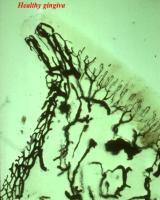

| Respuesta inmune El epitelio de unión y el epitelio de la bolsa son muy

permeables a moléculas

grandes que activan una reacción inmune en el tejido conjuntivo

gingival . En las fases tempranas en

esta reacción predominan los linfocitos para luego aparecer las

células plasmáticas y en

forma tardía predomina la infiltración inmune. La reacción inmune

genera los mediadores que refuerzan la inflamación y el daño al

tejido. En particular la producción de citoquinas

es prominente. Estas substancias son moléculas muy

potentes que activan varios

eventos perjudiciales en

el tejido conjuntivo.

La inflamación

y las reacciones inmunes de la gingiva y el periodonto resulta en

que dichas estructuras funcionales son reemplazadas por tejido de

granulación, que continúa

creciendo apicalmente, facilitando

el desarrollo de placa bacteriana en la bolsa periodontal.

|